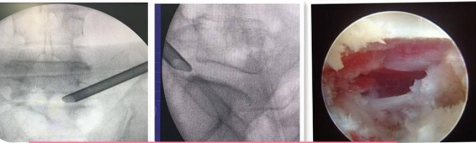

椎间孔镜技术:

利用椎间孔镜从患者腰椎侧方或者后方进入达到椎间盘突出或者其他病变部位,用专用工具将突出(脱出)的椎间盘组织或病变取出(去除)从而达到治疗椎间盘突出或者椎管狭窄的目的。它的优势在于:局部麻醉、微创、切口小(仅约7mm)出血少,恢复快(第二天即可佩戴硬腰围下地)及疗效好。

539650c2baae42ea976bd4bf6a4f7947.Png